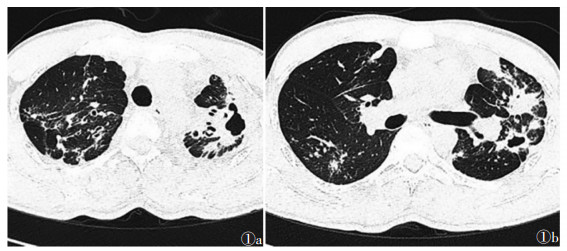

MDR-PTB组支气管扩张、病变累及肺叶≥3叶、厚壁空洞(壁厚>3 mm)、多发空洞(≥ 3个)、包裹性积液、胸膜增厚、病情进展情况均较DS-PTB组高,差异均有统计学意义(均P<0.05)(图 1a,1b);肺气肿、肺不张、支气管播散、渗出性病变、纤维化病变、钙化、空洞伴液平、胸腔积液情况差异均无统计学意义(均P>0.05)(表 2)。

| 注:患者,男,32岁,复治MDR-PTB。图 1a,1b 为CT平扫示双肺多肺叶浸润性病变,伴多发性空洞形成(部分呈厚壁特征),以及广泛支气管扩张改变 图 1 耐多药肺结核(MDR-PTB)的CT图像 |